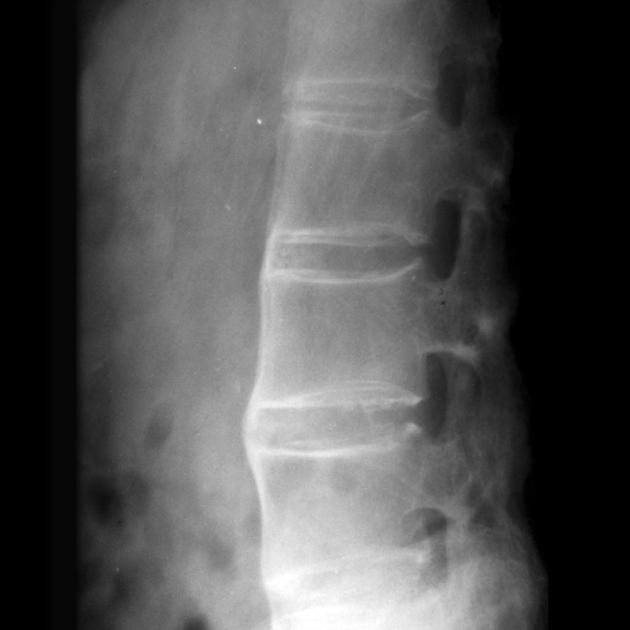

二、骨质疏松与脊柱骨折的预防策略

强直性脊柱炎患者发生骨质疏松的风险比普通人高3-4倍,这就像房子的地基不稳,随时可能出现"坍塌"